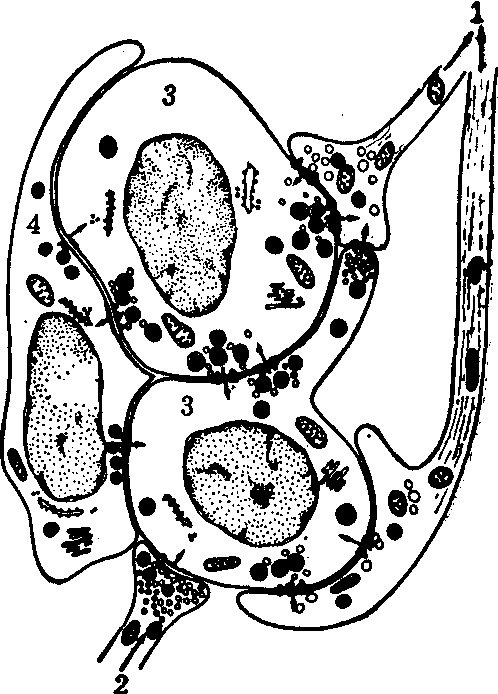

颈动脉体有结缔组织被膜包裹,实质由密集的上皮样细胞和丰富的毛细血管组成。上皮样细胞聚成不规则的团或索,毛细血管分布于细胞之间。光镜下,上皮样细胞的胞质着色很浅,根据细胞形态的特点,将细胞分二型。电镜的研究,对细胞分型的见解不一,但大多同意有二型细胞。一种细胞称Ⅰ型细胞或球细胞,数量多,常呈圆形,中等大小,胞质较丰富,有突起。它的主要特点是胞质有许多含致密核心的小泡,含多巴胺或5-羟色胺。另一种细胞称Ⅱ型细胞或支持细胞,形状较扁长,常围绕Ⅰ型细胞,胞质不含小泡或颗粒。Ⅰ型细胞上常有传入神经纤维的突触,并见交感节前纤维的突触。相邻的Ⅰ型细胞并有交互突触(见图)。

大鼠颈动脉体的超微结构

1.舌咽神经传入纤维 2.交感神经节前纤维 3.Ⅰ型细胞 4.Ⅱ型细胞